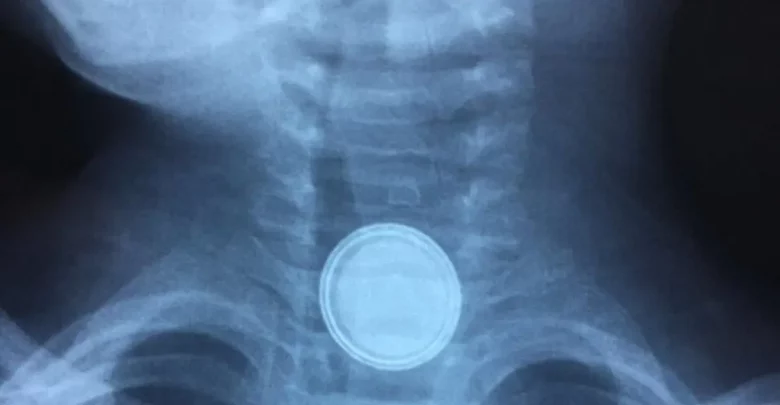

حرير- قال أحد المواطنين إن ابنه، البالغ من العمر عامين ونصف، تعرّض لمضاعفات صحية خطيرة عقب ابتلاعه بطارية صغيرة استقرت في المريء، ما استدعى تدخّلًا طبيًا عاجلًا لإخراجها في مستشفى البشير.

وأوضح أن حالة الطفل تدهورت بعد الإجراء الطبي، حيث ظهرت عليه أعراض نزيف حاد، قبل أن تُظهر الفحوصات وجود ثقب في المريء وتأثّر أحد الشرايين الرئيسية المرتبطة بالقلب، الأمر الذي استدعى متابعة طبية مكثفة.

وأوضح المدير الطبي في مستشفيات البشير الدكتور مؤيد القضاة، في تصريحات إذاعية، ن ما رواه والد الطفل يندرج ضمن تسلسل المضاعفات المعروفة لابتلاع البطاريات، لافتًا إلى أن المادة القاعدية تحللت داخل الجسم وتسببت بحدوث ثقب في المريء، ما أدى إلى تضرر الشريان الأبهر المجاور، وهو الشريان الرئيسي المسؤول عن ضخ الدم إلى الجسم، إضافة إلى احتمالية تأثر العصب الأبهر.

وبيّن أن الطفل خضع لعملية جراحية نوعية استمرت نحو 8 ساعات، تم خلالها علاج الثقب وإجراء رقع للشريان الأبهر.